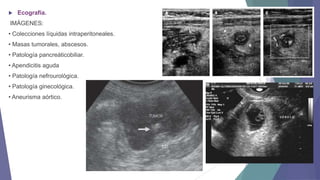

Ecografía.

IMÁGENES:

• Colecciones líquidas intraperitoneales.

• Masas tumorales, abscesos.

• Patología pancreáticobiliar.

• Apendicitis aguda

• Patología nefrourológica.

• Patología ginecológica.

• Aneurisma aórtico.

 Ecografía. IMÁGENES: • Colecciones líquidasintraperitoneales. • Masas tumorales, abscesos. • Patología pancreáticobiliar. • Apendicitis aguda • Patología nefrourológica. • Patología ginecológica. • Aneurisma aórtico.